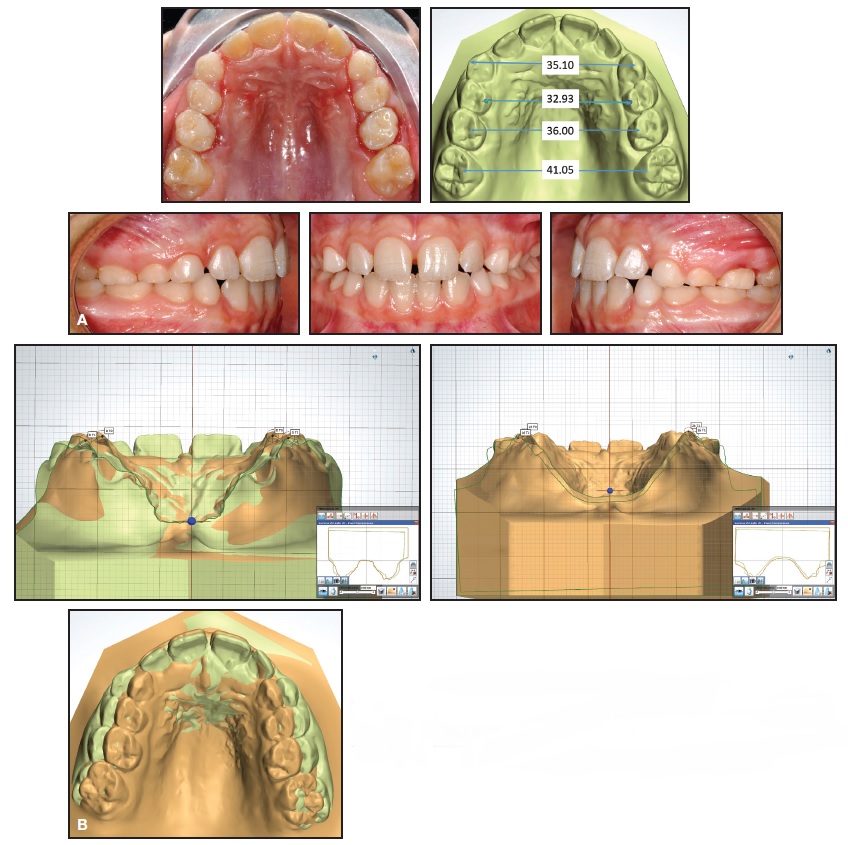

An 8-year-old female in the mixed dentition presented with a crossbite associated with a left lateral deviation of the mandible and a transverse deficiency (Fig. 4).

Fig. 4 Case 1. A. 8-year-old female patient with maxillary transverse deficiency, crossbite, and mandibular deviation before treatment. B. Arch-width measurements (mm) on STL digital casts obtained from laboratory scan of polyvinyl siloxane impressions.

A Leaf Expander was bonded to bands on the second deciduous molars, with extensions to the canines and first deciduous molars (Fig. 5A).

The screw was activated following the described protocol to produce 6mm of expansion (Fig. 5B).

Fig. 5 Case 1. A. Leaf Expander in place. B. After six months of expansion.

Including three months of passive retention, total treatment time was nine months. The crossbite and midline deviation were corrected, the archform was improved, and the first permanent molars (especially the right one) exhibited spontaneous expansion and rotation (Fig. 6, Table 1). Results remained stable nine months after treatment (Fig. 7).

Fig. 6 Case 1. A. After three months of retention. B. Superimposition of pre- and post-treatment results on palatal rugae.